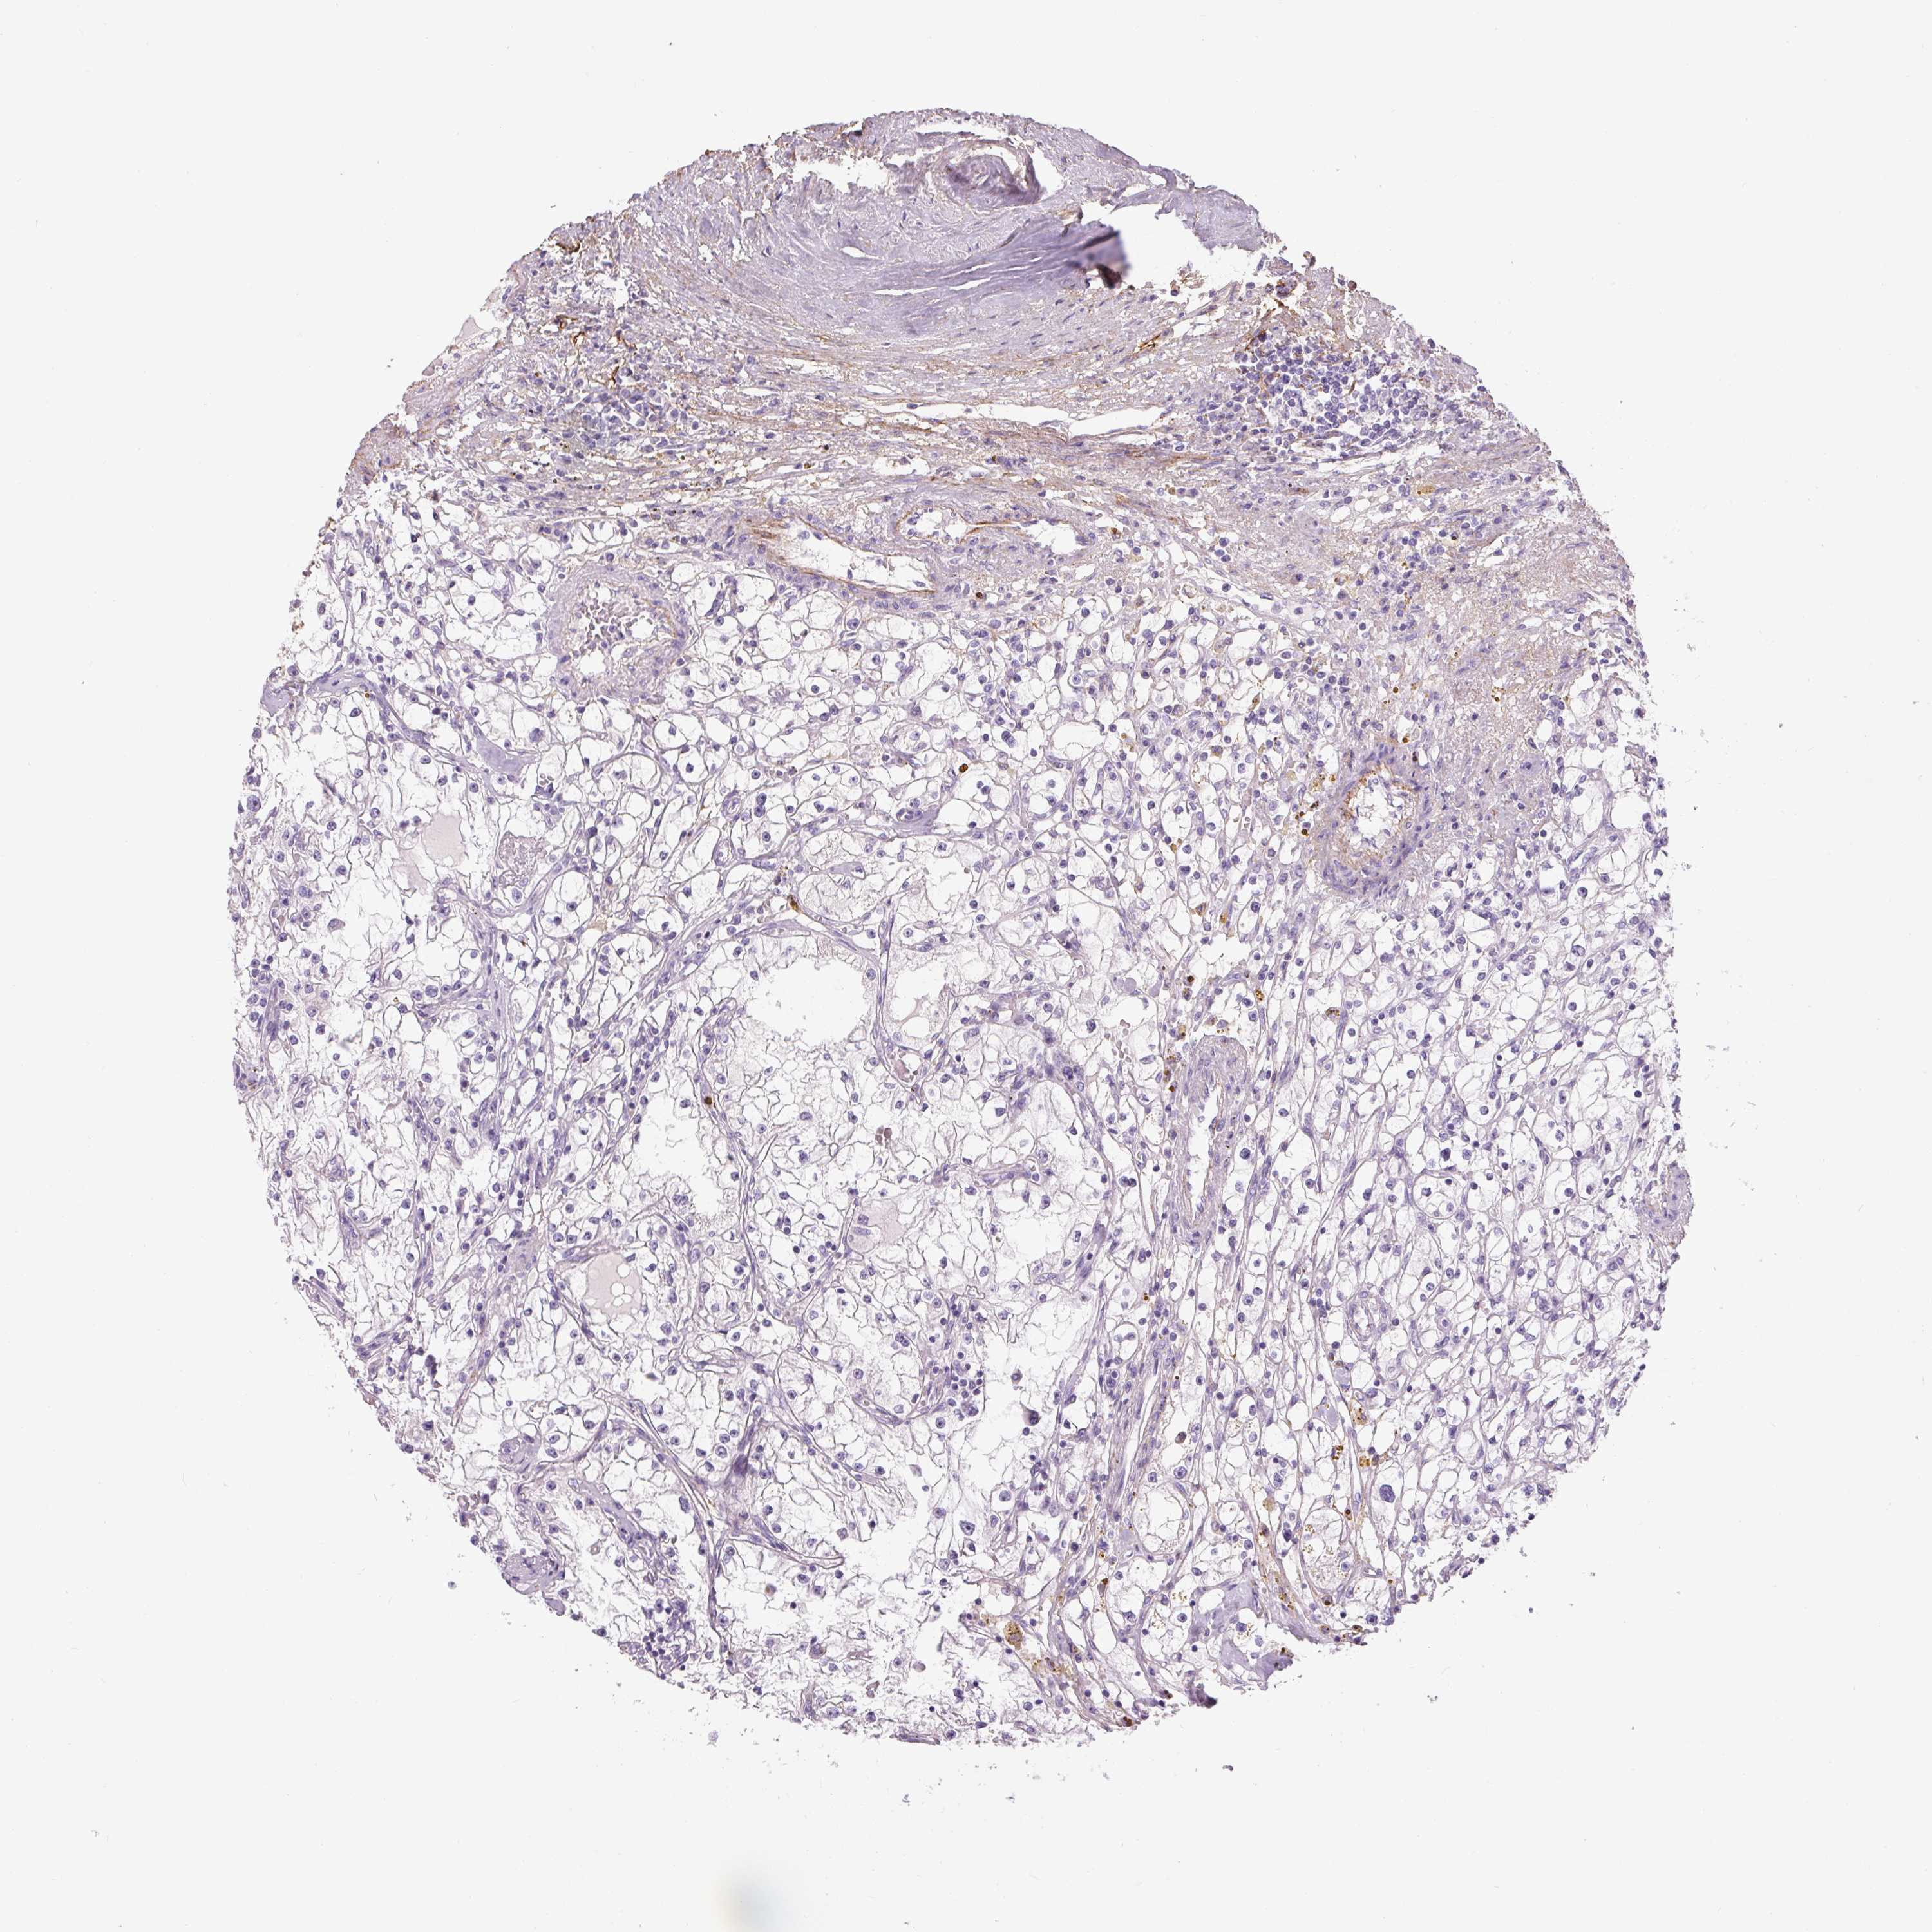

KIDNEY RENAL CLEAR CELL CARCINOMA (VALIDATION) - Interactive survival scatter ploti

The Survival Scatter plot shows the clinical status (i.e. dead or alive) for all individuals in the patient cohort, based on the same data that underlies the corresponding Kaplan-Meier plots. Patients that are alive at last time for follow-up are shown in blue and patients who have died during the study are shown in red.

The x-axis shows the expression levels (FPKM) of the investigated gene in the tumor tissue at the time of diagnosis. The y-axis shows the follow-up time after diagnosis (years). Both axes are complimented with kernel density curves demonstrating the data density over the axes. The top density plot shows the expression levels (FPKM) distribution among dead (red) and alive patients (blue). The right density plot shows the data density of the survived years of dead patients with high and low expression levels respectively, stratified using the cutoff indicated by the vertical dashed line through the Survival Scatter plot. This cutoff is automatically defined based on the FPKM cutoff that minimizes the p-score. The cutoff can be changed by dragging the vertical line or by entering a cutoff value in the square labeled "Current cut-off".

Under the Survival Scatter plot the p-score landscape (black curve; left axis) is shown together with dead median separation (red curve; right axis). Dead median separation is the difference in median mRNA expression between patients who have died with high and low expression, respectively. It is calculated as follows: median FPKM expression of dead patients with high expression - median FPKM expression of dead patients with low expression. This is intended to aid the user in visually exploring custom cutoffs and the associated p-scores and dead median separation.

Individual patient data is displayed and can be filtered by clicking on one or more of the category buttons on the top of the page. Categories describing expression level and patient information include: high, low, alive, dead, female, male and tumor stages. The scale of the x-axis can be toggled between linear and log-scale by clicking on the "x log" button. Mouse-over function shows TCGA ID, patient information and mRNA expression (FPKM) for each patient.

& Survival analysisi

Kaplan-Meier plots summarize results from analysis of correlation between mRNA expression level and patient survival. Patients were divided based on level of expression into one of the two groups "low" (under cut off) or "high" (over cut off). X-axis shows time for survival (years) and y-axis shows the probability of survival, where 1.0 corresponds to 100 percent.

FBN1 is not prognostic in Kidney Renal Clear Cell Carcinoma (validation)

: 6.16

Average pTPM 7.1

Number of samples 100